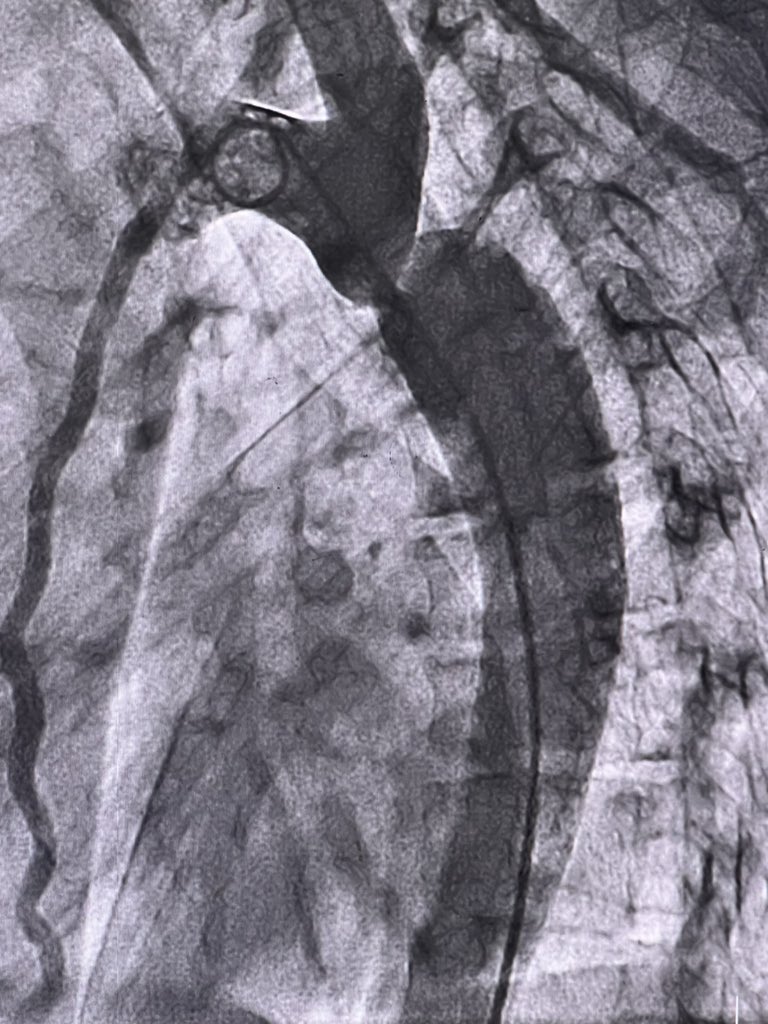

Great learning cases today. Successful COA stenting….Thanks to my mentors #Interventionalfellow #NICVD.